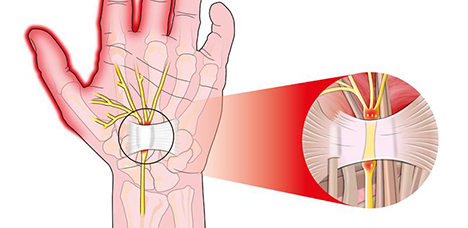

손목터널증후군

손목 안쪽 신경이 지나가는 통로가 좁아지는 질환